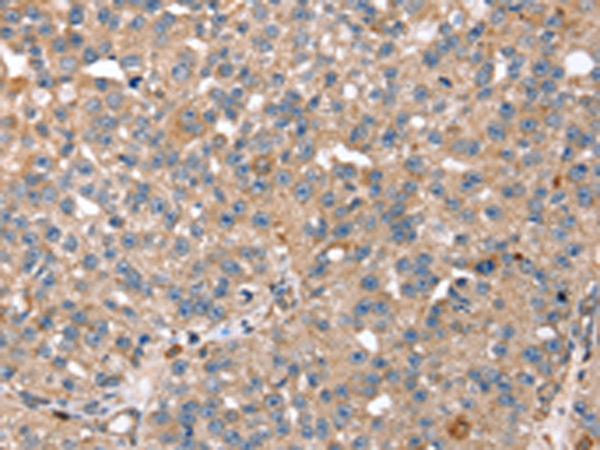

分类: 科研抗体货号: P08692别名: RGP4; SCZD9应用: IHC反应种属: Human, Mouse, Rat